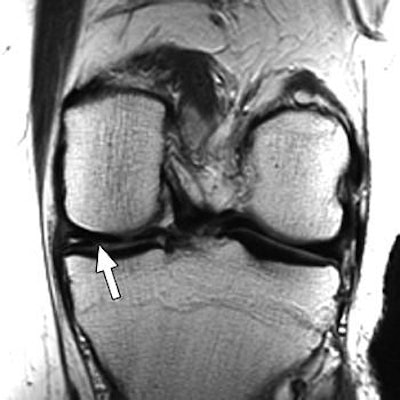

| Above, 27-year-old man with meniscal tear. Coronal 2D fast spin-echo (FSE) image (TR/TEeff, 4,000/38) shows tear (arrow). Middle, coronal 3D FSE extended echo-train acquisition (XETA) image (TR/TEeff, 2,500/38). Tear (arrow) was visible on two images of 2D FSE acquisition and 12 of coronal 3D FSE XETA images. Below, sagittal reformation of 3D FSE XETA dataset shows tear (arrow). |

Imaging at 3 tesla improved the resolution of 3D FSE XETA to 0.6-mm isotropic compared with 0.7-mm isotropic for 1.5-tesla images, the authors stated. In the volunteer with knee pain, 3D FSE XETA and 2D FSE revealed a meniscal tear in the posterior horn of the medial meniscus. Still, on the 3D FSE XETA, the tear was visible on a dozen images in the coronal plane versus two images from the 2D FSE acquisition.